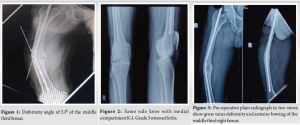

A 53-year-old male came to SGT hospital with gross deformity of the right thigh of 14 years duration and pain over the medial side of the knee for 6 months with a VAS score of 7. The patient gives a history of a road traffic accident in December 1991, in which he sustained a right femur shaft fracture, for which he was operated on with a K-nail. He gives a history of re-trauma after 2 months of surgery in which he sustained an injury on the operated side. He did not undergo any surgery 2nd time. The patient gives a history of gradual increase in deformity of the right thigh for a few years following re-trauma. Now, the patient came with a complaint of pain over the medial side of the knee joint for the last 6 months and deformity for 14 years. No other significant history or any comorbidities. Clinical assessment reveals a short limb gait and limb length discrepancy of 3 cm. He had gross varus deformity of the right thigh with right knee medial joint line tenderness. There was no significant muscle atrophy. He had a full knee range of motion and was able to squat and sit on a crossed leg. Spine, bilateral hip, and ipsilateral ankle examination findings were normal. Plain radiograph in two views demonstrated gross varus deformity of 23⁰ of the right middle third femur following malunion with broken K-nail at two places in situ (Fig. 1) with Kellgren–Lawrence Grade 3 knee osteoarthritis (Fig. 2). The deformity angle was 23°.

The apex of the deformity was at the middle third of the right femur. The lateral view of the femur revealed anterior bowing of the femur in the sagittal plane (Fig. 3). Malunited right femur shaft fracture with broken K-nail in situ with 3 cm shortening with secondary degenerative arthritis medial compartment right knee. Osteotomy at two levels (Fig. 4), realigning implant removal and internal fixation with interlocking nailing.